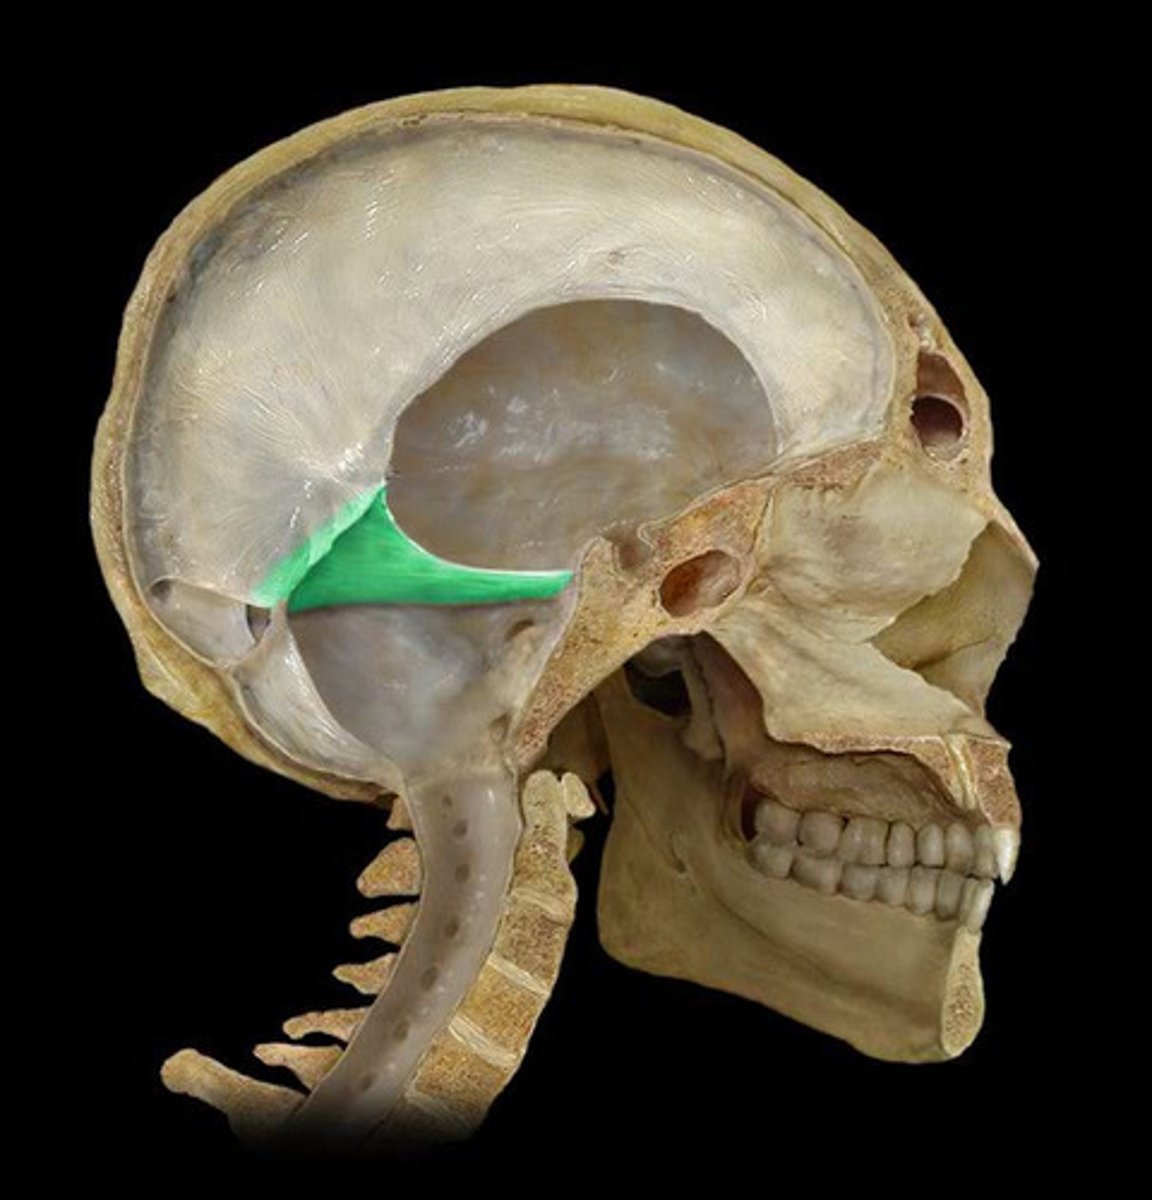

Superior Sagittal Sinus

falx Cerebri

tentorium Cerebelli

transverse Sinus

Falx Cerebelli

Dura Mater

Arachnoid Mater

Subarachnoid

Pia Mater